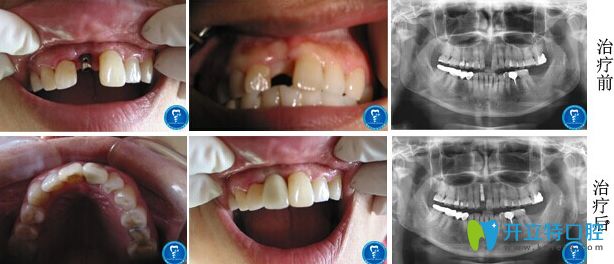

北京京通口腔怎么樣?張蓉醫(yī)生單顆牙缺失即刻種植修復(fù)前后對(duì)比圖:

種植牙前:意外導(dǎo)致上門牙斷掉半截,不但影響美觀,說(shuō)話還跑風(fēng);

種植牙后:在網(wǎng)上對(duì)北京京通口腔做了詳細(xì)的了解,才決定去做的種植牙修復(fù),即刻種植牙效果就是好,拔牙和種植牙全程用了不到兩個(gè)小時(shí),就重“新”長(zhǎng)出了牙齒,啃東西還有外觀都和真牙一模一樣!